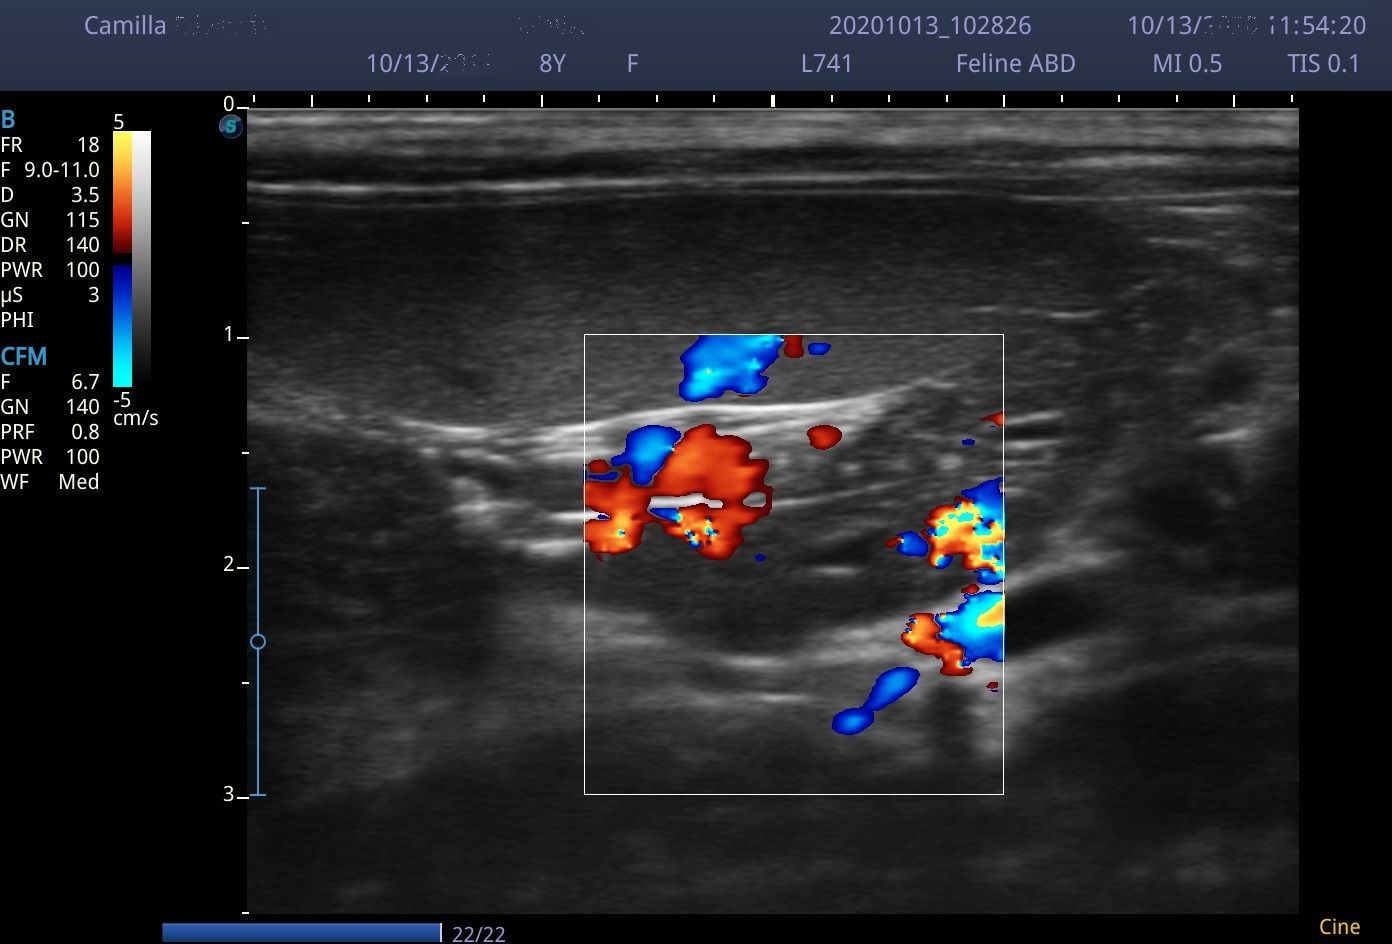

I scanned with the microconvex C613 probe (4-13MHz) and the linear L741 (4-6MHz). Although the linear probe gives great images, the 4.5cm footprint does make maneuverability around a small cat abdomen a little tricky. I used the microconvex probe was used in a few dogs and cardiac cases and it held up well.

Images from the E2V